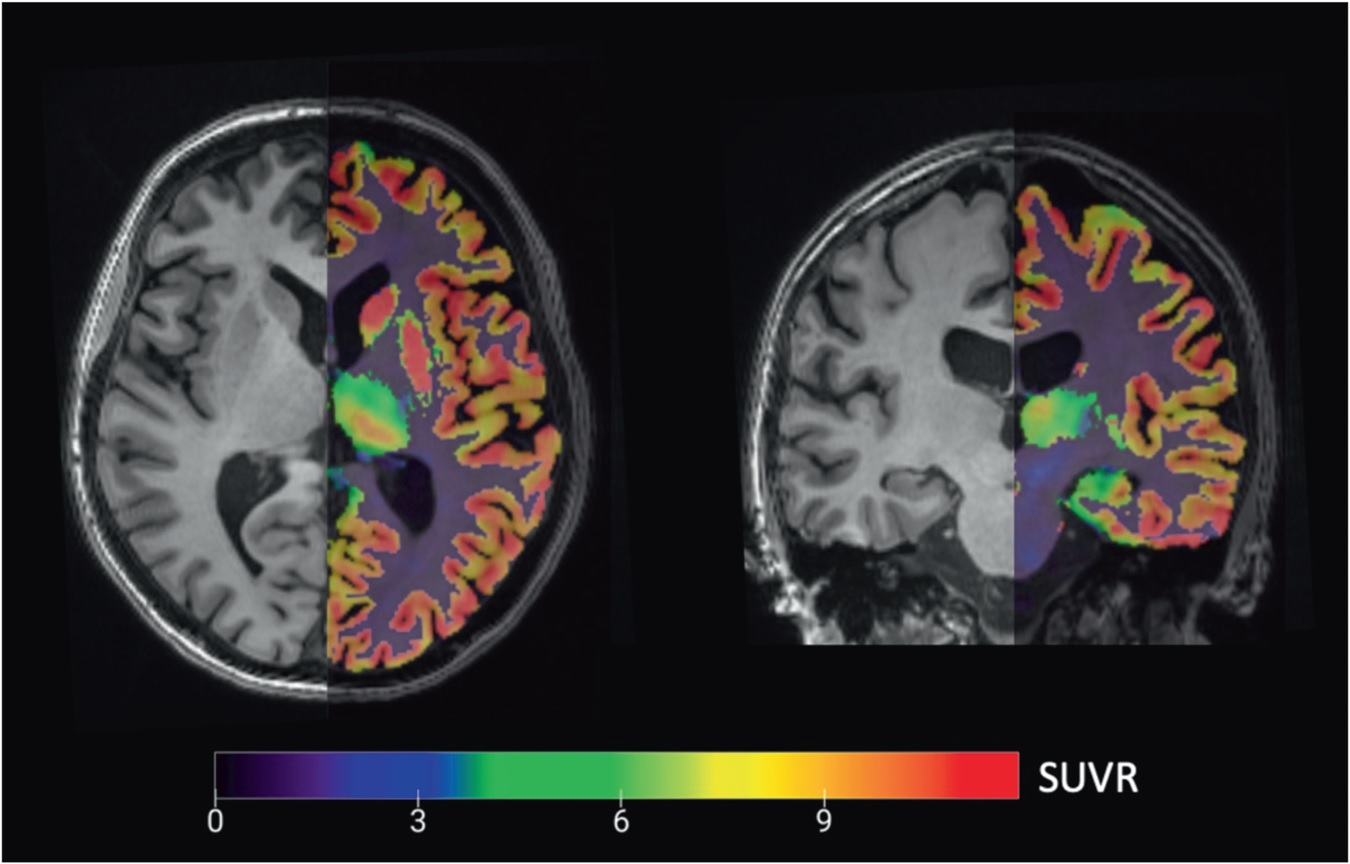

Isoprotrace is designed for prostate cancer patients and is indicated for PET imaging, for primary staging of those with high-risk prior to primary curative therapy, and for patients who have suspected recurrence based on elevated serum prostate-specific antigen (PSA) level. Isoprotrace is a single sterile vacuum-vial kit, intended for preparing multi-patient doses of gallium-68 (Ga-68) gozetotide (PSMA-11) within five minutes.